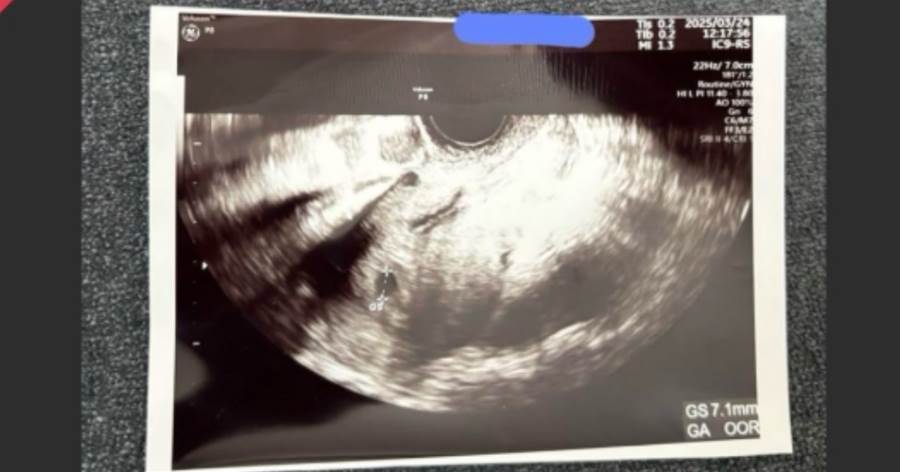

彼女から“妊娠したから金払って”→エコー写真まで送られてきたが、調べた結果“全員同じ画像”だったと気づいた話